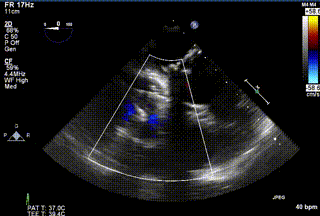

2021年12月24日,復旦大學附屬中山醫院葛均波院士團隊成功應用LuX-Valve Plus為一例極重度三尖瓣反流(TR)合并房顫、房缺的患者完成了經血管三尖瓣置換術,這是在前基礎上,本周完成的第三例經血管三尖瓣置換手術,葛均波院士、周達新教授等與心外科魏來教授、賴顥教授,心超室的潘翠珍教授、李偉教授及麻醉科的郭克芳教授共同完成了本周手術,均獲得圓滿成功!患者術后超聲顯示無TR,臨床癥狀明顯改善。本周手術的成功也為LuX-Valve Plus救治性臨床研究添上了濃墨重彩的一筆。

三例患者入院后,葛均波院士團隊周達新教授、潘文志教授、張源博士、陳莎莎博士及心超室的潘翠珍教授、李偉教授對患者的情況進行詳細評估和討論,最終決定為三例患者選擇LuX-Valve Plus40mm、50mm和50mm型號的瓣膜進行手術治療。手術后即刻拔除氣管插管,術后患者三尖瓣反流癥狀得到顯著改善,復查心超結果顯示人工三尖瓣瓣膜支架固定穩定,瓣葉關閉形態未見異常,未見明顯反流。